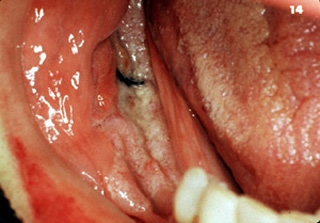

Cáncer pequeño

La primera imagen muestra una lesión roja pequeña, granular

o atercipelada (ver flecha) en el suelo de la boca adyacente al conducto de Wharton. Esto es totalmente

asintomático y solo se percive como un ligero espesamiento de la

mucosa. El paciente puede curarse si la enfermedad se descubre en esta fase; sin embargo,

este tipo de lesión puede no ser detectada en el examen oral y desde

luego continúa creciendo. (Photograph courtesy of Dr. S. Rovin.) |